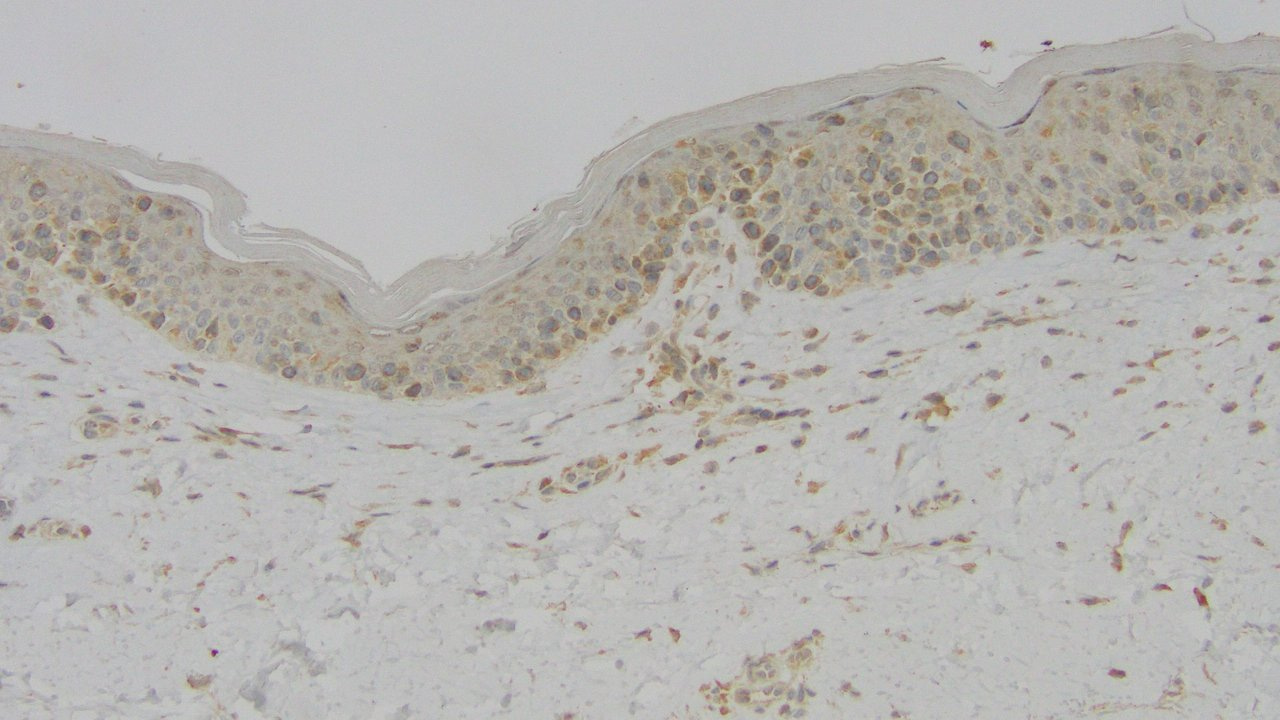

Peter first assembled 42 cases of CGDTLs, the second largest cohort of its kind. During clinical annotation, he discovered that CGDTLs are highly heterogeneous. They can present in any of the three major layers of the skin: epidermis, dermis and subcutaneous adipose tissue. Superficial, epidermal infiltrates present as thin patches and plaques and are associated with a mixed prognosis. Deeper infiltrates in the dermis or fat present as nodules and are associated with near-uniformly fatal outcomes.

Because of this disease heterogeneity, Jay wanted to confirm the diagnoses via close examination of the gamma delta T cell receptor sequences. He thought it would be useful to confirm the cell of origin and assess the tumor purity. Strikingly, he found that all of the lymphomas of the epidermis and dermis are derived from the V delta 1 (Vd1) gamma delta T cell. In contrast, all of the panniculitic cases (centered in the subcutaneous fat) are derived from the Vd2 gamma delta T cell.

Jay hypothesized that these cells reflected the skin-homing gamma delta T cell in each skin compartment. Indeed, in non-diseased human skin, nearly all of the gamma delta T cells in the epidermis and dermis express the Vd1 receptor. In contrast, nearly all of the gamma delta T cells in the subcutaneous fat all express the Vg3 Vd2 receptor. In other words, by studying gamma delta T cell lymphomas, Jay uncovered an underappreciated cell type in the subcutaneous fat.